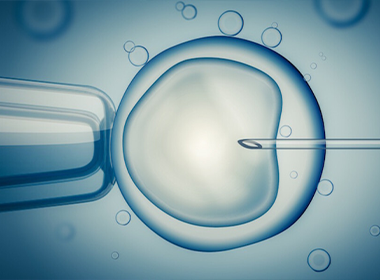

In Vitro Fertilization (IVF)

Assisted reproduction technique where eggs are fertilized outside the body and embryos are transferred to the uterus.

Intracytoplasmic Sperm Injection (ICSI)

An advanced IVF method where a single sperm is directly injected into an egg to aid fertilization.